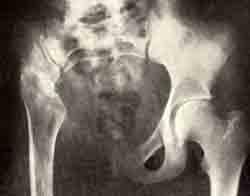

Кистозная форма остеобластокластомы

Кистозная форма остеобластокластомы лобковой, седалищной и подвздошной костей, принявшая литическое течение, после резекции и гомопластики.